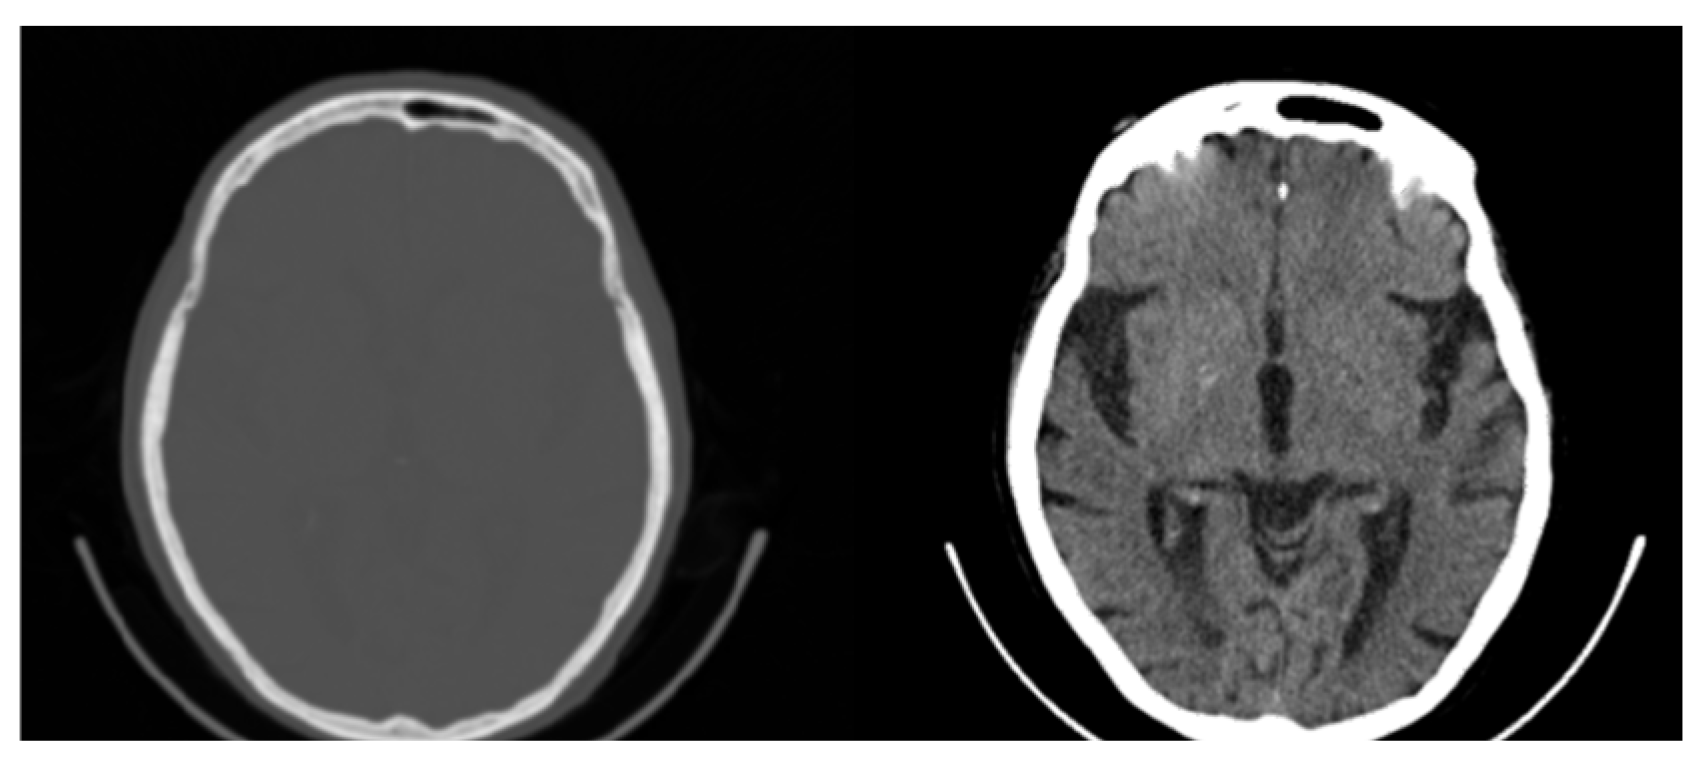

Figure 4.

Original CT slice (left) and windowed slice (right) with improved contrast. All possible 65,536 (16-bit) original values are mapped to 256 (8-bit) Gray values limiting the contrast and visibility of information.